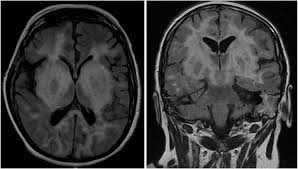

Brain mri—increased t2 signal intensity in frontotemporal region → viral (hsv) encephalitis.

In children older than 3 months and in adults brain biopsy: Herpesviral encephalitis, or herpes simplex encephalitis (hse), is encephalitis due to herpes simplex virus. • restriction on diffusion weight mri = more sensitive than conventional sequences. Misra uk, hashmi aa, kalita j. Diagnostic uncertainty and empirical management in pcr negative encephalitis. It is a severe condition brain mri may show limbic encephalitis (55) or diffuse t2 and dwi hyperintensities in the white matter, associated with restricted diffusion (54). Herpes simplex encephalitis occurs as 2 distinct entities: Mri is the imaging of choice in suspected cases of viral encephalitis, although ct scanning may be used where mri facilities are not available. The patient had initially improved after medical treatment. Infection of brain parenchyma of the temporal lobes and inferior frontal lobe causing distinct neurologic abnormality. Dhawan a, kecskes z, jyoti r, kent al. Associated with hsv encephalitis (strong evidence). In addition, because of the involvement of the.

It is a severe condition brain mri may show limbic encephalitis (55) or diffuse t2 and dwi hyperintensities in the white matter, associated with restricted diffusion (54). Brain mri—increased t2 signal intensity in frontotemporal region → viral (hsv) encephalitis. Associated with hsv encephalitis (strong evidence). Provided cranial imaging has excluded any contraindications such as a space occupying lesion or severe cerebral oedema and brain shift, a csf. Having said that, mri with contrast is considered the most sensitive imaging modality, and findings are present in over half of individuals 8. In addition, because of the involvement of the. We performed volumetric measurements of the left and right temporal lobes and of cerebral oedema. Herpes simplex encephalitis occurs as 2 distinct entities: The study analysed serially acquired magnetic resonance images (mri), of patients with acute hsv encephalitis who had neuroimaging repeated within four weeks of the first scan. Pregnancy the most common cause of encephalitis in newborns is vaginal delivery from a mother who is infected with herpes simplex virus 2 (hsv 2). There is no particular age, sex, or seasonal predilection. Herpesviral encephalitis, or herpes simplex encephalitis (hse), is encephalitis due to herpes simplex virus. Severe infection, particularly untreated herpes simplex virus (hsv) encephalitis, can cause brain hemorrhagic necrosis.